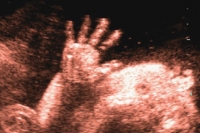

Una manina speciale

Questa foto meravigliosa denominata "Fetal Hand Grasp" , letteralmente " la mano del feto che si aggrappa" è stata…